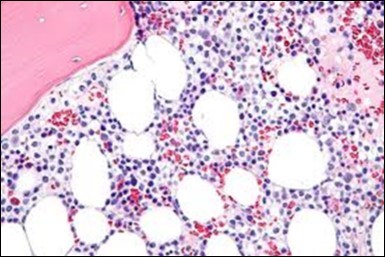

Figure 8.HCL: widely disseminated hairy cells within the bone marrow trabaculae(24).

Figure 9.HCL: hairy cells within a bone marrow trephine biopsy(25).

The classic hairy cell is medium sized with a magnitude of 10-14µm. The moderately abundant or variable cytoplasm may be transparent or mildly basophilic. The cellular surface with the characteristic serrated perimeter depicts innumerable fragile or stout extensions of cytoplasm ,particularly discernible on the phase contrast and electron microscopy. The cytoplasm may exhibit vacuoles with occasional azurophilic granules4. The nucleus may be elliptical or reniform, folded or indented with a coarse, reticulated or a finely dispersed chromatin and inconspicuous nucleoli along with infrequent mitosis. Bone marrow aspiration or bone marrow trephine biopsy may be inadequate for diagnosis in 30%-50% individuals4. The trephine sections of the bone marrow may depict a characteristic interstitial pattern of leukaemic infiltration. Generally the bone marrow is hyper-cellular, though it may be hypo-cellular in 10-15% individuals4. The leukaemia cell ingress may be diffuse or partial, although diffuse infiltration is frequent. The partial variety of leukaemic dissemination may be ineptly categorized with an indeterminate differentiation from the uninvolved marrow. The malignant insertions may initially emerge as miniature, undefined, cellular loci. The formalin fixed, paraffin embedded sections may elucidate a crystalline zone or a “halo” appearance of the cells with a circumscribed nucleus on account of the plentiful cytoplasm4. The cellular margins may be intertwined. Fixation of bone marrow smears with Zenker’s fixative may demonstrate a retracted cytoplasm of the hairy cells with a consequent disconnected structure. The bone marrow in the absence of a malignant process may be hypo-cellular or hyper-cellular. Reticulin stains may delineate an enhanced accrual of broad, dense reticulum fibres surrounding the aggregates of leukaemia cells with the fibrous circumlocution of individual malignant cell and fibrotic extensions into the abutting, uninvolved bone marrow4.

The leukaemia cells may enunciate a characteristic immune phenotype, crucial for a confirmatory diagnosis. The peripheral blood mononuclear B cell population may display a kappa or lambda light chain restriction. The phenotype of classic hairy cell leukaemia may be delineated by concurrent, immune reactive CD19+ CD20+,CD 11c+, CD25+, CD103+ and CD123+. An intensely immune reactive CD200+ and a non reactive CD27- antigen may be present2, 4. Evaluation of a trephine bone marrow biopsy and bone marrow aspirate may define the degree of tumour infiltration. A dry tap on account of prominent bone marrow fibrosis may be elucidated at preliminary diagnosis. A decline in the normal haematopoiesis may account for a hypo-cellular marrow in 10% instances. Gradation of cellular infiltrating of the leukaemia within the bone marrow may be appropriately investigated with immune –histochemical stains2, 4. Immune staining for CD20+, annexin 1 and VE1 (a BRAF V600E stain] may validate the diagnosis and precisely analyse the extent of malignant bone marrow infiltration[8]. Determination of BRAF V600E mutation may be critical in therapeutically non responsive individuals with applicable standard therapy or in instances of multitudinous reoccurrences[9]. Deploying inhibitors of BRAF V600E gene may be efficacious in patients impervious to approved therapy. The mutation necessitates a comprehensive scrutiny of the implicated individuals with a sensitive molecular assay which may discern up to < 10% of the hairy leukaemia cells appearing in the peripheral blood smears or bone marrow aspirates diluted with peripheral blood or aspirates elucidating a dry tap[2,4]. Allele specific polymerase chain reaction (PCR) or a next generation sequencing may be optimally employed to circumvent false negative outcomes. If the leukaemia cells are sparse or if particularly sensitive & efficacious molecular techniques are not accessible, the application of appropriate immune histochemical stains to the bone marrow biopsy such as a BRAF V600E mutation stain (VE1) may detect the hairy cells and conclusively diagnose the condition[2,4,10]. Figure 1, Figure 2, Figure 3, Figure 4, Figure 5, Figure 6, Figure 7, Figure 8, Figure 9, Figure 10, Figure 11, Figure 12, Figure 13, Figure 14.